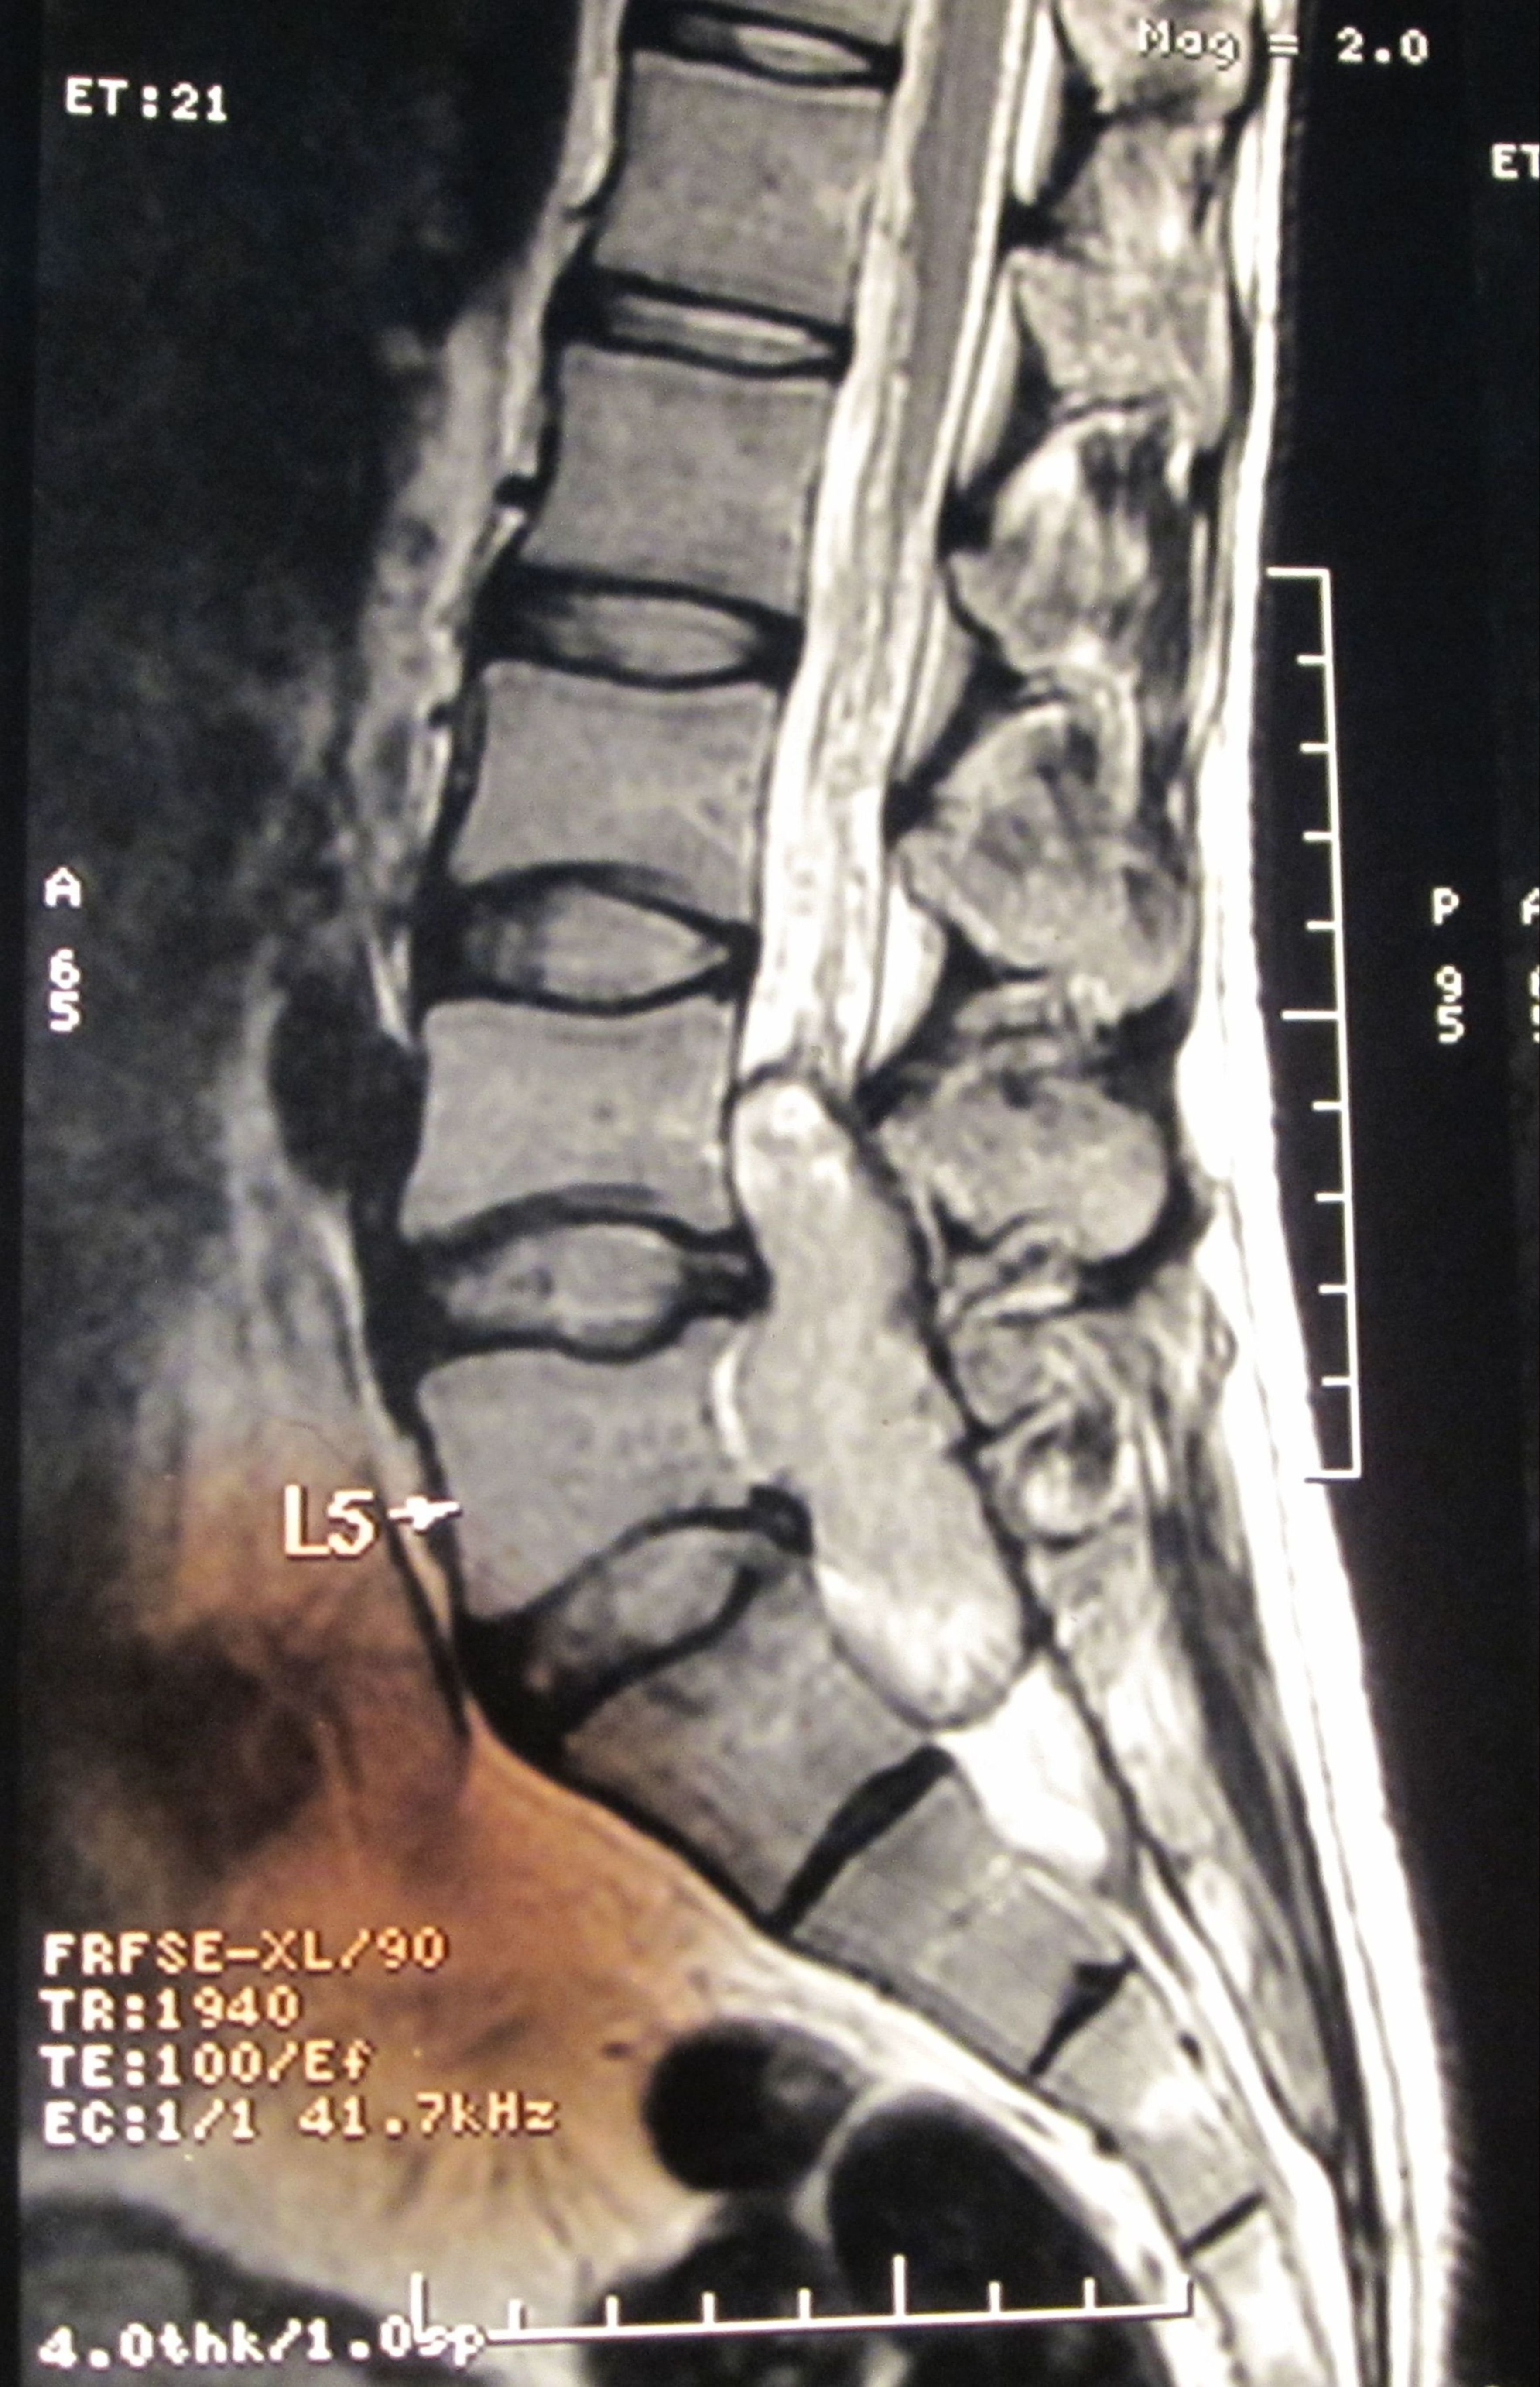

Filum terminale paraganglioma is a rare tumour with usual short segment spinal involvement (one or two segments) as described in various literatures. It can also present with long segment spinal involvement as in our case, the tumour has involved L4 to S1 segments. Prognosis of filum terminale paraganglioma is excellent after total excision as it is classified under WHO grade I tumor. Nonetheless, after subtotal removal, tumour recurrence can occur. Even such an extremely rare entity with a larger spectrum of presentation can be treated successfully by total removal of the tumour. Here we present a fi lum terminale paraganglioma which was diagnosed after histopathology and immuno-histochemistry. Patient made a full recovery after tumour removal.